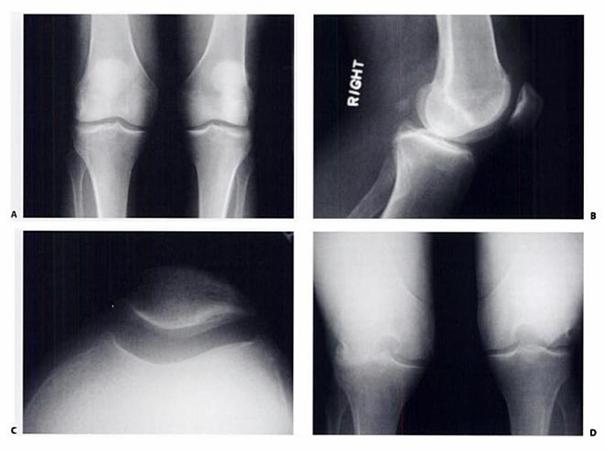

Scorul Outerbridge:

I. Inmuierea si aparitia de cavitati intracartilaginoase,

II. Aparitia fisurilor,

III. Fisuri si fasciculari ale cartilajului,

IV. Denudarea osului subcondral.

Fig.15. A- radiografie antero-posterioara ; B- radiografie laterala; C-

vedere axiala a patelei; D- radiografie